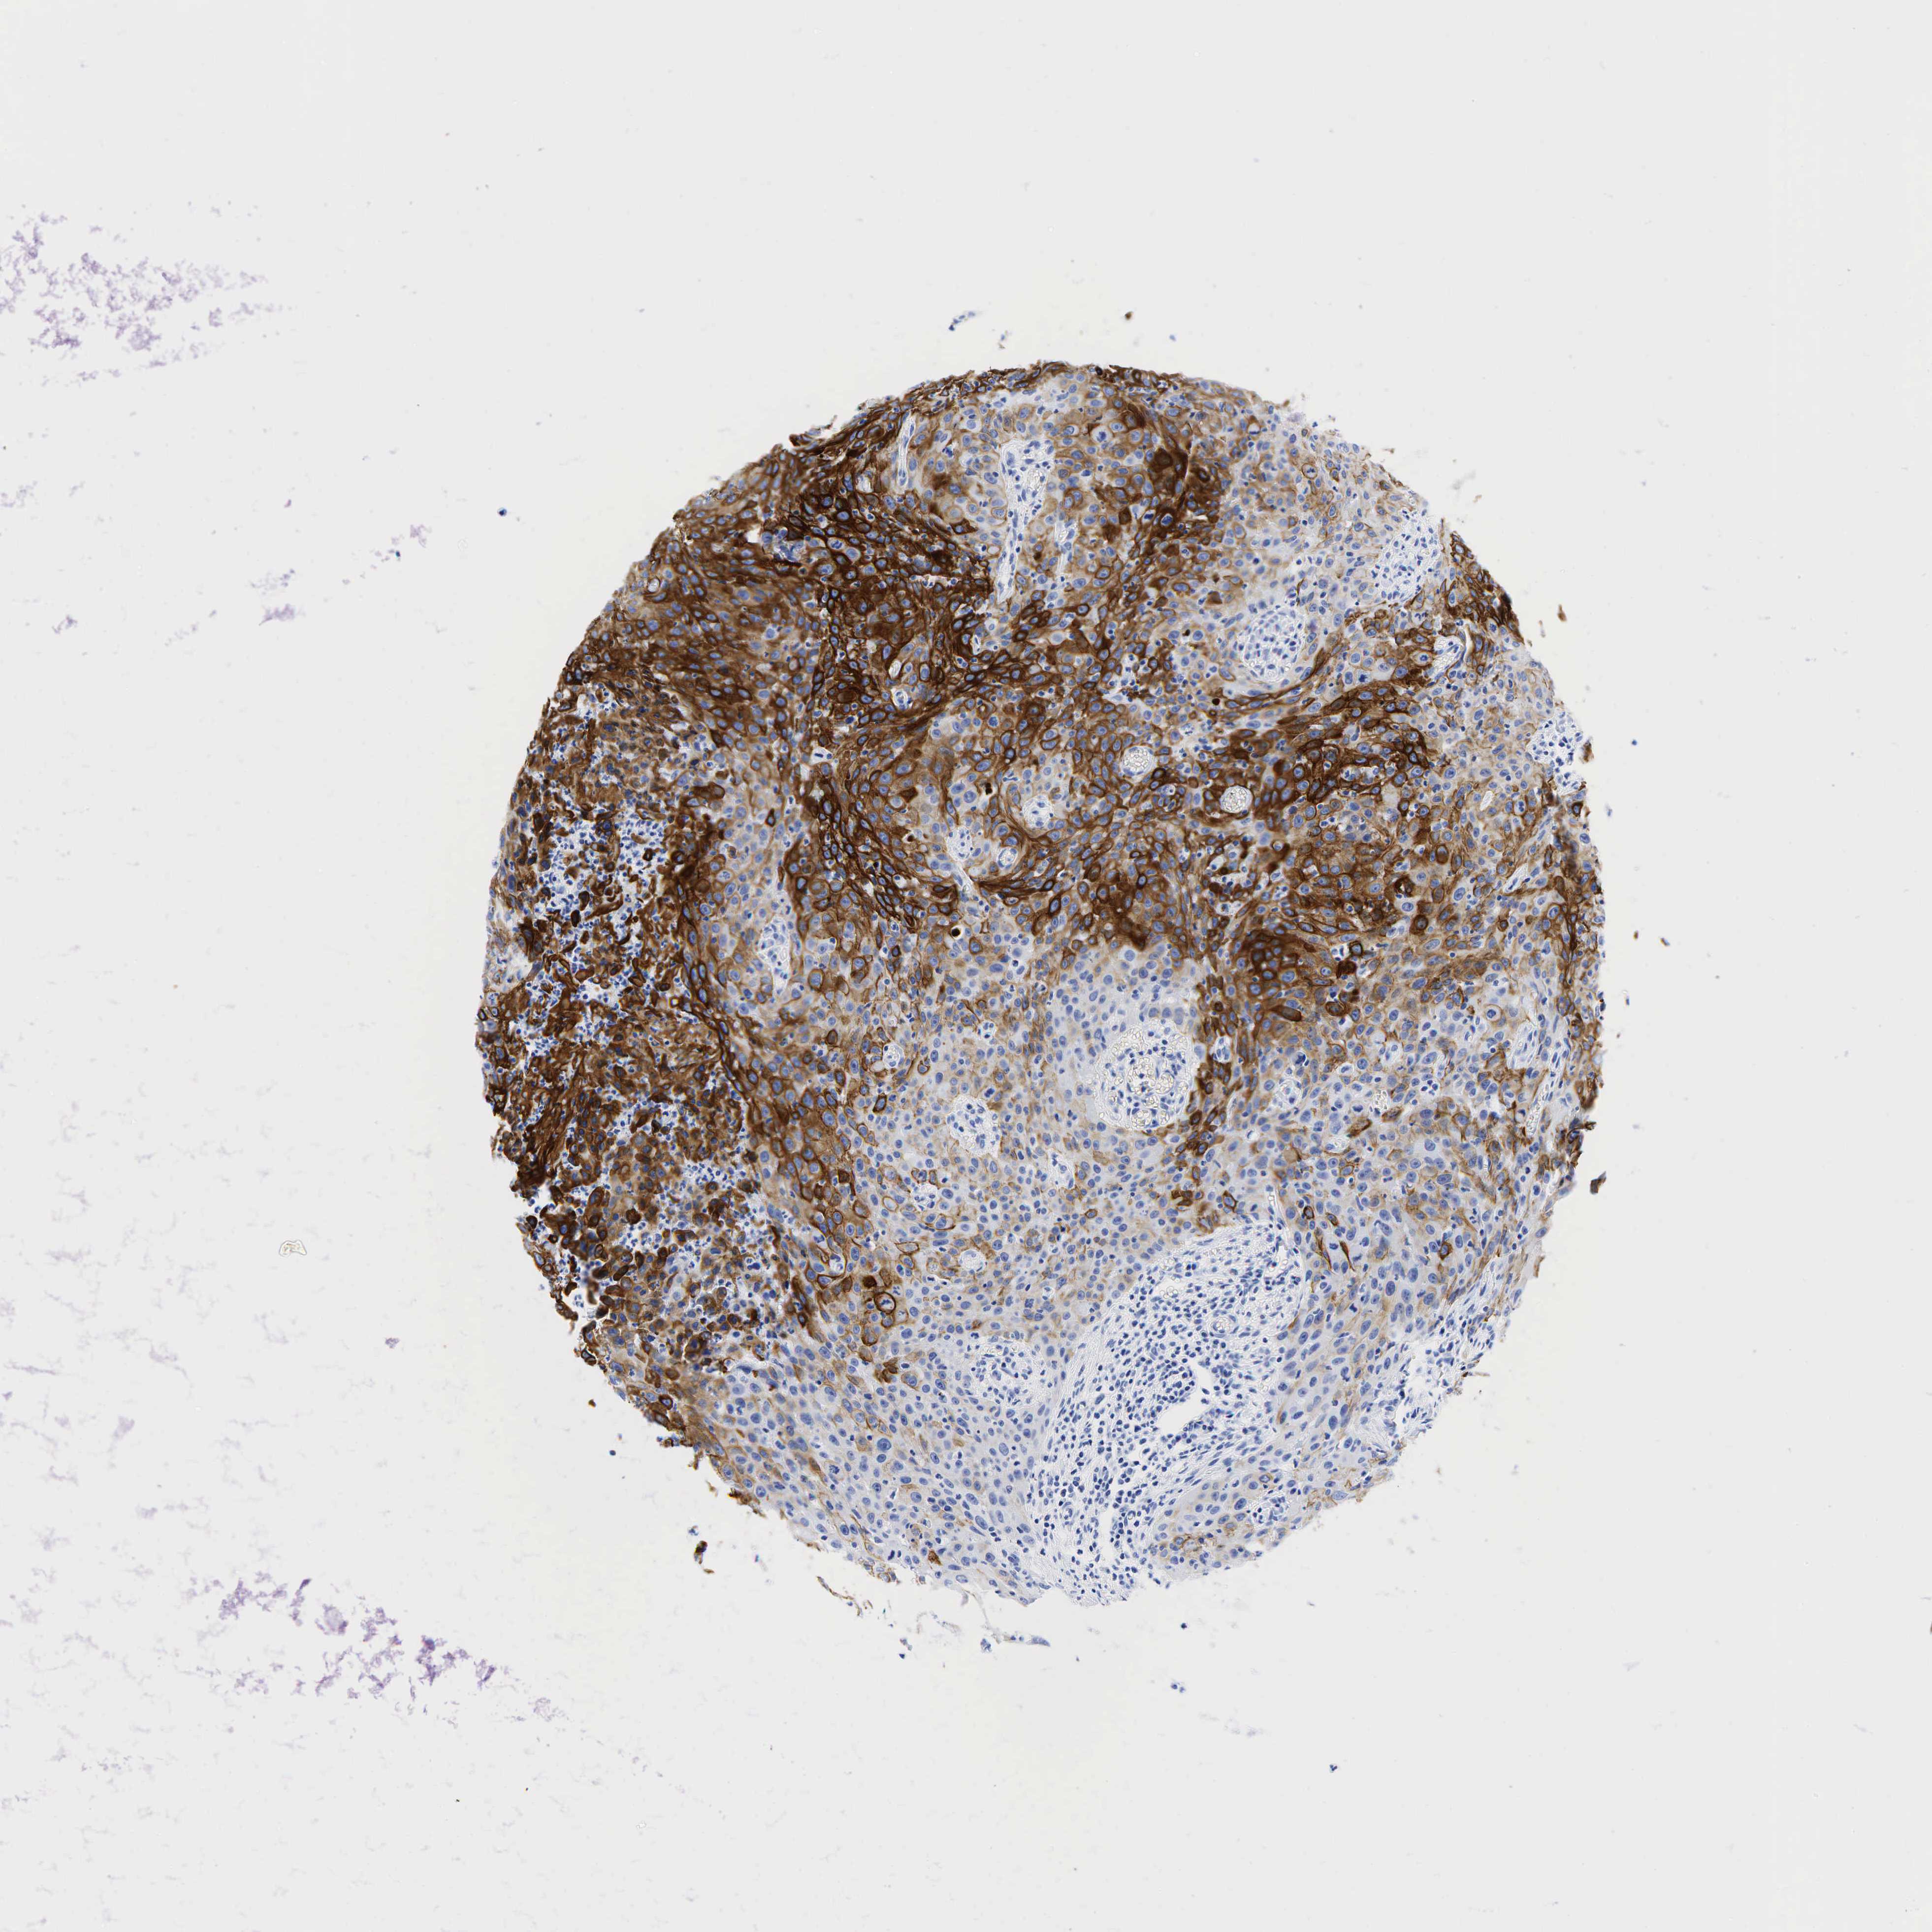

UROTHELIAL CANCER - Protein expressioni

A mouse-over function shows sample information and annotation data. Click on an image to view it in a full screen mode. Samples can be filtered based on level of antibody staining by selecting one or several of the following categories: high, medium, low and not detected. The assay and annotation is described here.

Note that samples used for immunohistochemistry by the Human Protein Atlas do not correspond to samples in the TCGA dataset.

Antibody stainingi

Antibody staining in the annotated cell types in the current human tissue is reported as not detected, low, medium, or high, based on conventional immunohistochemistry profiling in selected tissues. This score is based on the combination of the staining intensity and fraction of stained cells.

Each image is clickable and will lead to virtual microscopy that enables deeper exploration of all samples and also displays staining intensity scores, fraction scores and subcellular localization as well as patient and tissue information for each sample.

Antibody HPA002465

Antibody CAB000031

Urothelial carcinoma, High grade

Urothelial carcinoma, Low grade

Adenocarcinoma, NOS